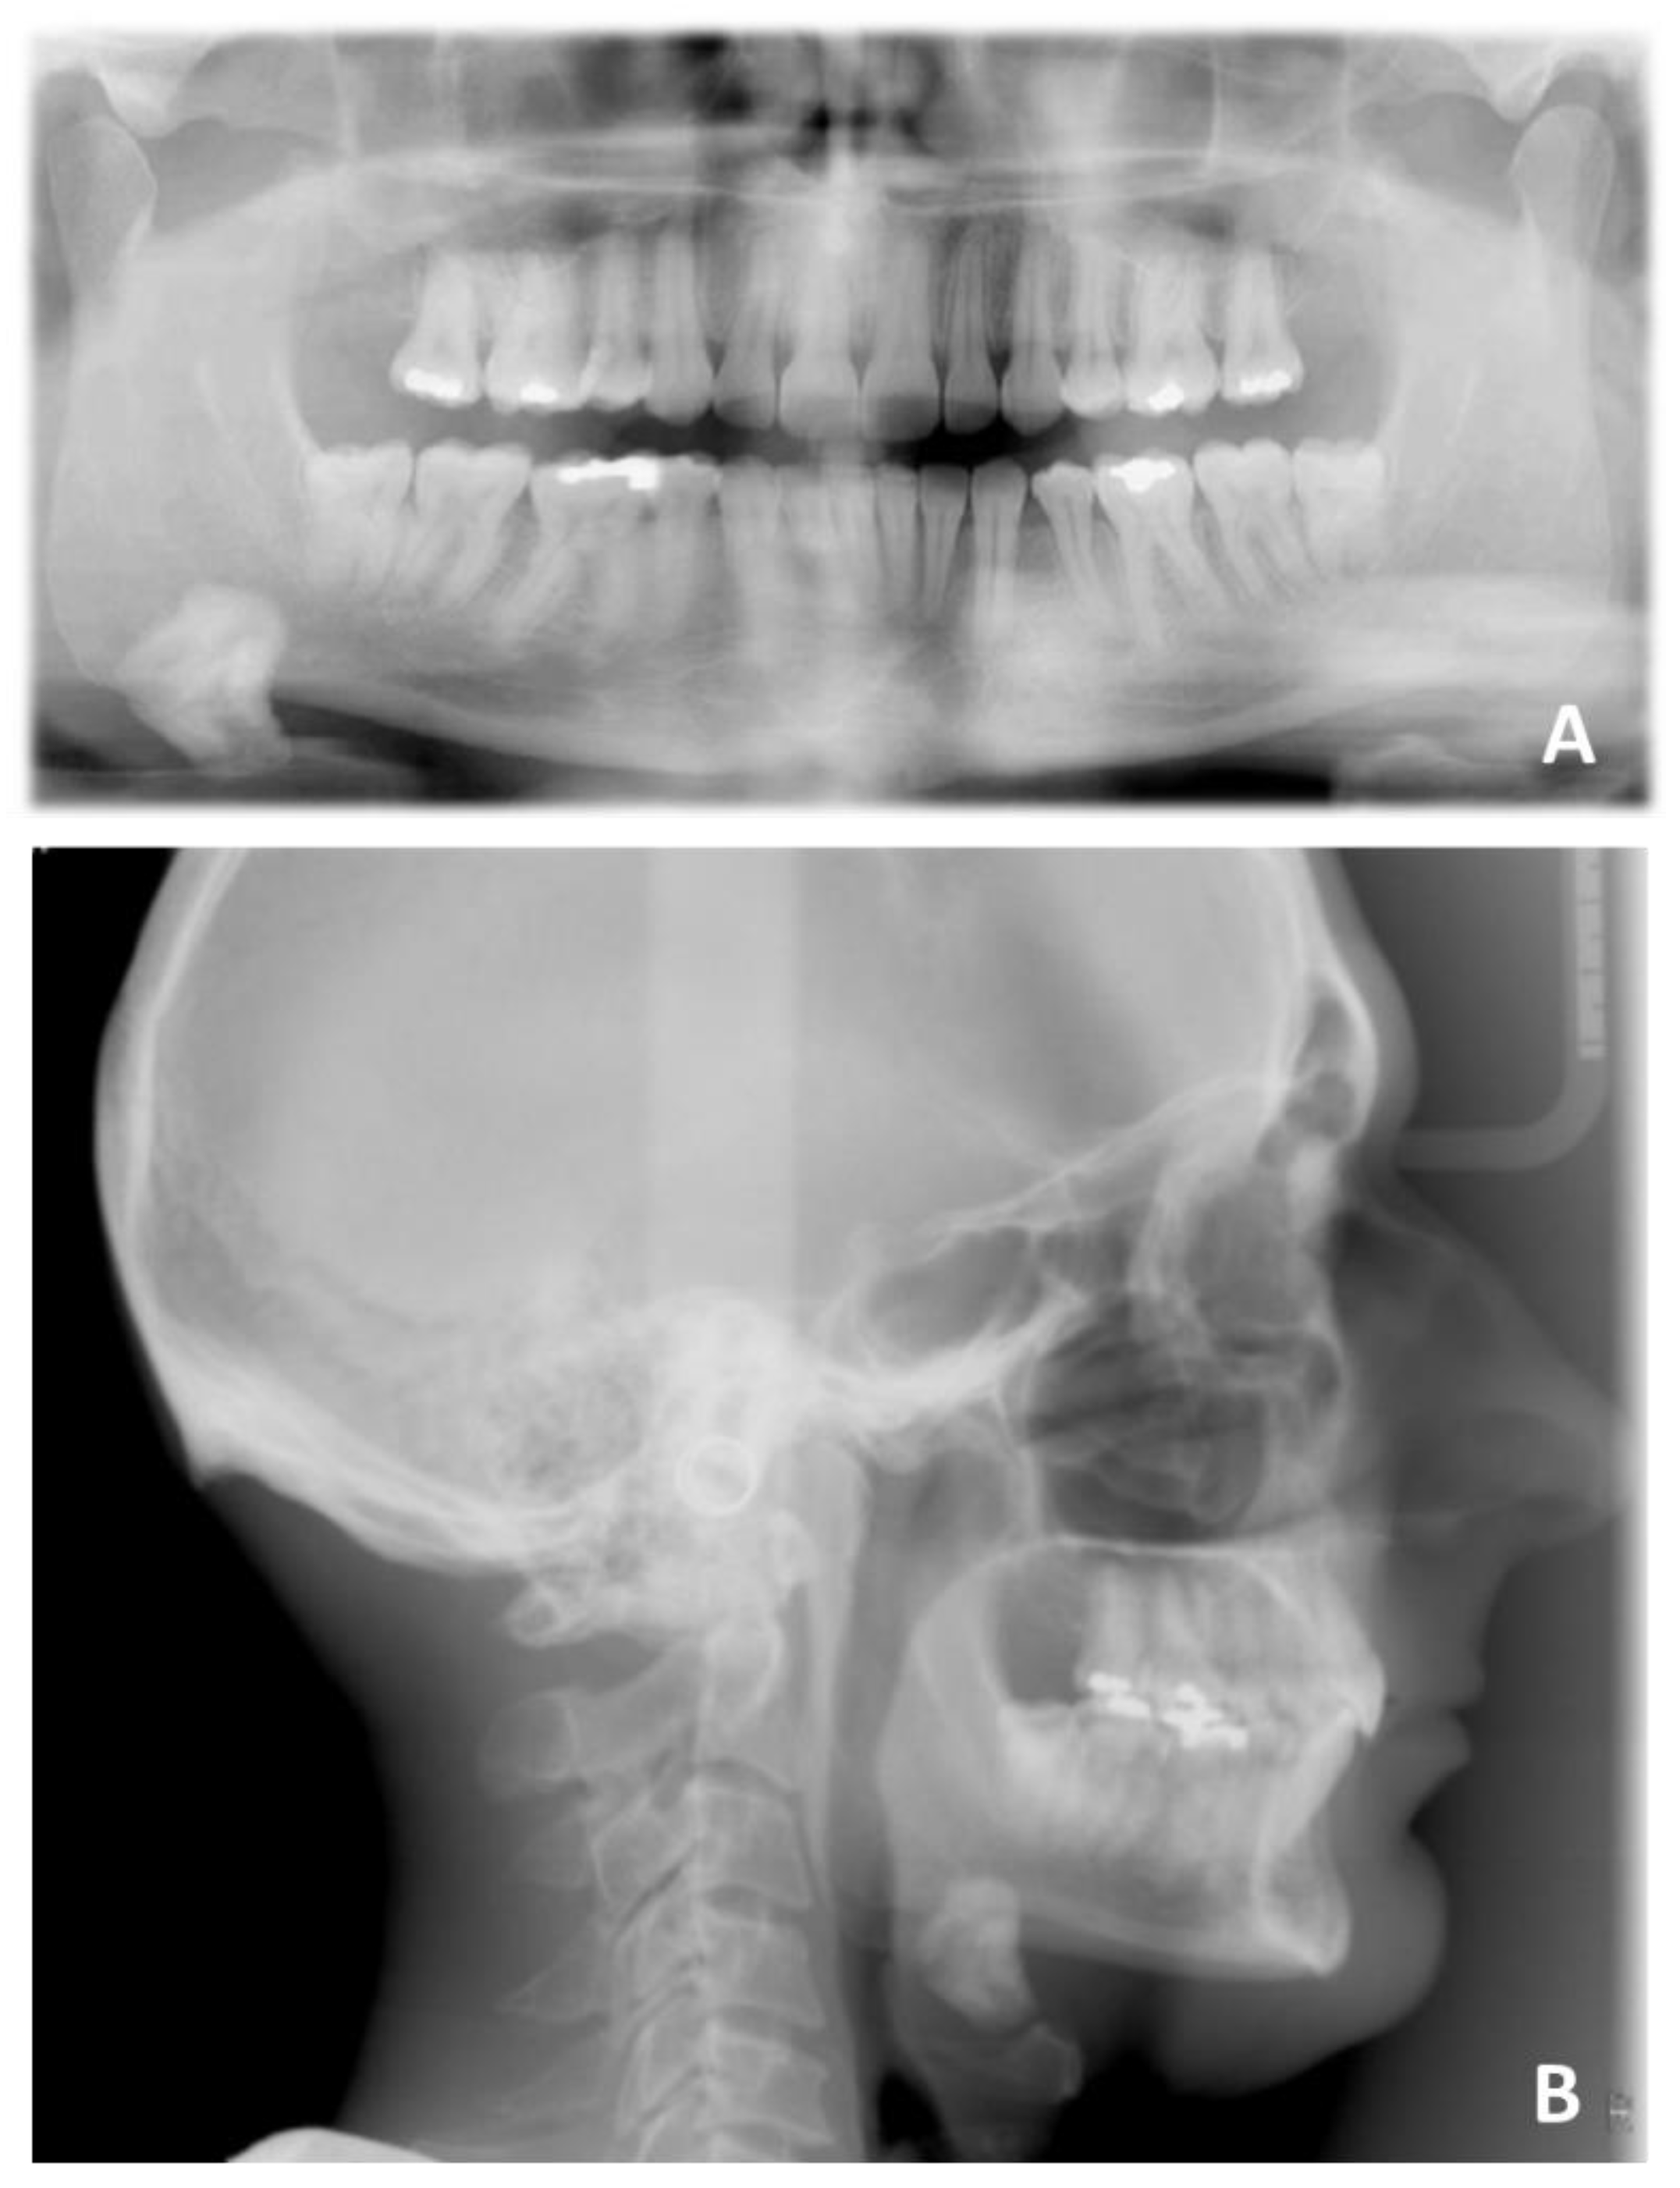

Figure 16. Pre-treatment radiographic of case number 2: (A) orthopantomography; (B) lateral cephalogram.

The second case was concerned with the orthodontic treatment with transparent aligners of a growing patient with dentoskeletal class II malocclusion, scissor bite of the first right upper premolar, a slight contraction of the upper and lower arches, lower dental crowding and an interincisive diastema.

The patient also had good exposure to their smile and deep bite, so it was indicated to correct the deep bite by leveling the lower arch with the intrusion of the canines and incisors (Figure 15 and Figure 16).

The patient presented a skeletal class II malocclusion, a normodivergent growth pattern, excessive proclination of the upper incisors and a normoinclination of the lower incisors (Figure 17 and Table 3).